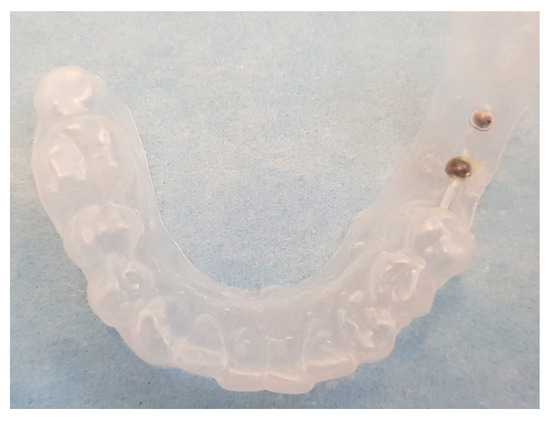

| Templates | 12 | 6 | 5 | 23 |

| Spheres | 12 | 12 | 15 | 39 |

Initial identification of hypothetical implant sites (panoramic radiograph) | Drawing (permanent marker) of the implant sites on a plaster cast | Template construction |

CBCT taken with template | Definitive patient selection Elegibility criteria: fixture position confirmed by CBCT |